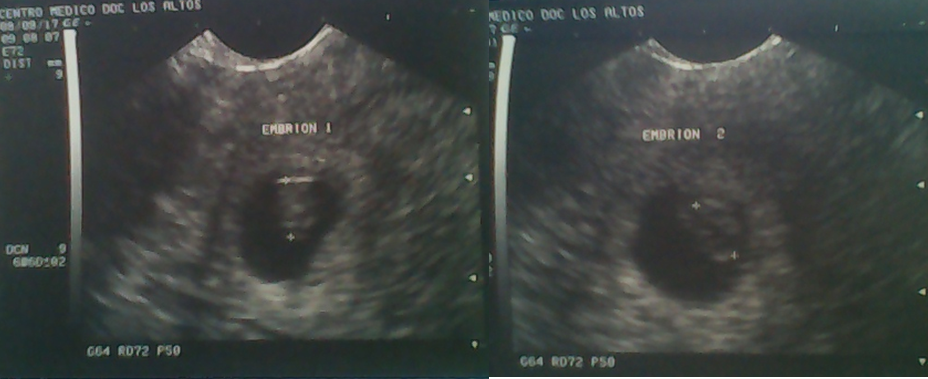

In fact, I would define that day as the second most frightening day of my life, but why the second? Well, keep reading and you will know. It turns out that these weeks we were dedicated to carrying out tests to confirm pregnancy, however we had not been able to go to the Obstetrician, so we did not have any pregnancy confirmation echogram, until at the beginning of August 2017, my partner was to the consultation accompanied by my mother (for work reasons I could not go) and finally the information was confirmed with an echo, however, said echo came with a small surprise ... they were twins!

That day was the most terrifying of my life! Imagine! I worried about everything that had to have a child and now it turns out that there are two! With a job that did not allow me to live well alone, in a country where there is no guarantee of anything, without housing, without opportunities and with two babies! HAHA! I remember it at this moment and it makes me laugh. Oh! and not satisfied with all this, one has to show integrity and comfort the mother, after all, they carry the bulk of the situation both physically and emotionally, then I wanted to jump off a bridge but I had to be a man xD. It turns out that it was a funny situation, because I was in classes and I went to answer the call, when I came back I interrupted the class and I stayed stunned repeating "are two" obviously the class was dedicated to hear that I was going to be a dad, and I was even given the opportunity to present the evaluation of that day at another time (that would be my face).